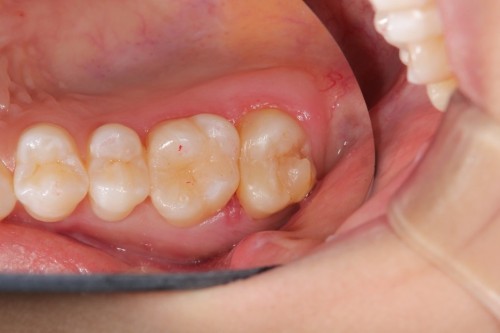

両奥に白い詰め物で治療してありますが、詰め物の周りが茶色に着色しています。また、本来の歯の形とはずいぶん違うみたいです。奥歯で噛んだ感じに違和感があるとの事でしたので、治療致しました。本来歯が持っている形をお口の中で作って行きます。

治療後です。どこを治療したのかわからないくらい『自然の歯』の様にできました。噛む時の違和感もなくなり、硬い物でも噛める様になりました。

左右奥歯のダイレクトボンディング

費用5万円×2本

リスクとして欠ける可能性がある(修復可能)。